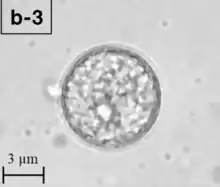

| A Balamuthia mandrillaris cyst | |

Balamuthia's lifecycle, like the Acanthamoeba, consists of a cystic stage and a non-flagellated trophozoite stage, both of which are infectious, and both of which can be identified in the brain tissue on microscopic examination of brain biopsies performed on infected individuals. The trophozoite is pleomorphic and uninucleated, but binucleated forms are occasionally seen. Cysts are also uninucleated, possessing three walls: an outer thin irregular ectocyst, an inner thick endocyst, and a middle amorphous fibrillar mesocyst.[9]